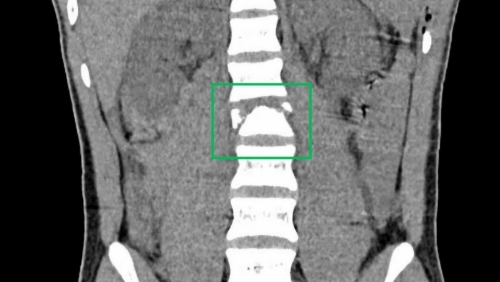

Những cơn đau bụng âm ỉ, đầy hơi và tiêu chảy kéo dài khiến bệnh nhân L.H.B (63 tuổi, ở TP Hồ Chí Minh) nghĩ rằng mình chỉ bị rối loạn tiêu hóa thông thường. Tuy nhiên, kết quả kiểm tra sức khỏe lại cho thấy bệnh nhân mắc lymphoma không Hodgkin ruột non – một dạng ung thư ruột non hiếm gặp.